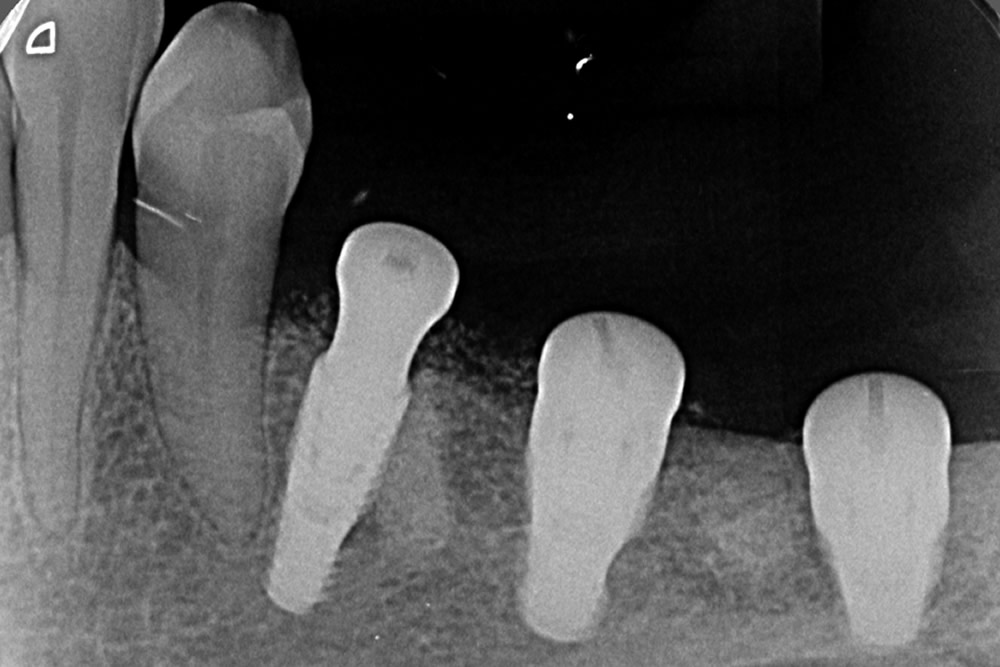

Próteses Fixa sobre implante

É utilizada para substituir ,através de implantes intra-ósseo, dentes já condenados que foram, ou ainda precisam ser extraídos. É a melhor opção capaz de restabelecer função mastigatória, conforto e estética, seja em casos de reabilitação de um único dente ou até de uma arcada dentária inteira (protocolo). As próteses sobre implante podem ser produzidas com diversos materiais, e esta escolha se torna fundamental para um resultado estético favorável.